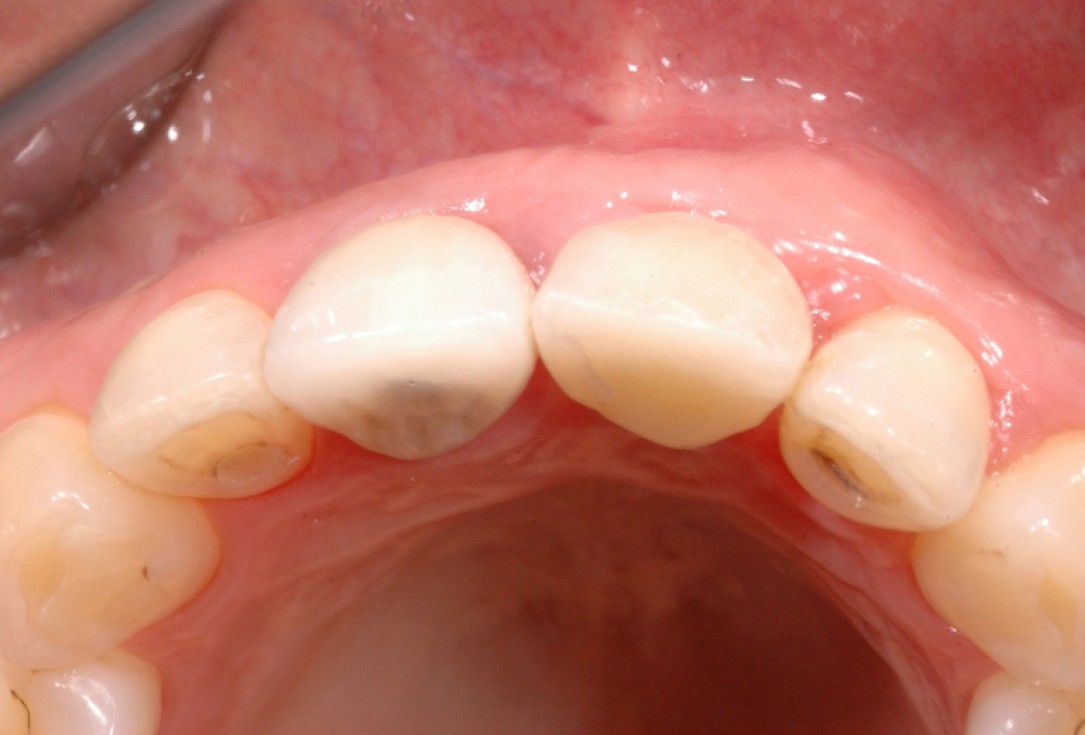

16/18 - Final restoration 15 months after implantation and stability of root coverage in regio 23GBR together with soft tissue augmentation with mucoderm® and maxresorb® - Dr. S. Scherg

17/18 - Final restoration 15 months after implantationGBR together with soft tissue augmentation with mucoderm® and maxresorb® - Dr. S. Scherg